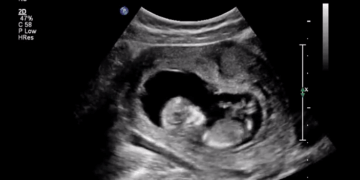

Abortion Advocates Resort to Lies. The Truth is Pro-Life Laws Have Killed 0 Women

Wisconsin and Texas may seem like a world apart — or at least, a country’s width apart, with politics as different as their weather. But two abortion stories out of these not-so-similar states lend credence to a shared truth: The “health of the…